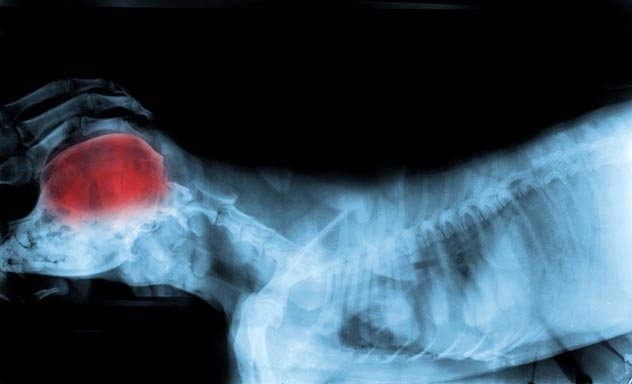

Собаки - складні істоти. Їх мозок не обмежується трьома командами: «сидіти», «лежати» й «принести». Навіть якщо ви не є власником собаки, ви повинні знати, що вони є одними з найрозумніших істот на планеті. Собаки можуть навіть страждати від тих же недуг, які впливають і на мозок людини. Вони, звичайно, не в змозі вирішувати лінійні рівняння, але вони можуть зрозуміти більше, ніж ви думаєте. До вашої уваги 10 цікавих фактів про розум собаки.